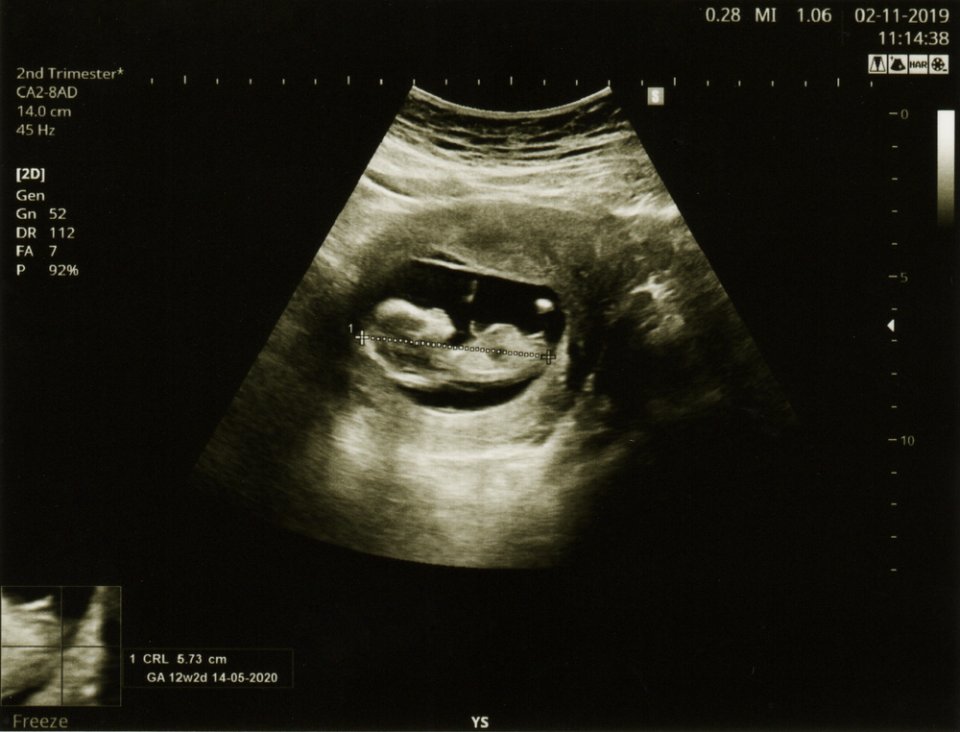

13 haftalık gebelik görüntüsü ile bebek önceki haftalara göre çok daha net görülebilir. 4D ultrason cihazları kullanılarak yapılan taramalarda bebeğin gülümsemesi veya çeşitli yüz ifadeleri bile görülebilir. Hızlı deri ve kemik gelişimi ile bebek bu hafta itibariyle insan formuna daha da yaklaşır. Beyin gelişiminin diğer organlardan daha erken olduğu için bebeğinizin başı vücuduna kıyasla büyük görünecektir. İstemli hareketler henüz olmasa da ultrasonda bebeğin bazı hareketleri belirlenebilir. Genellikle 13.haftada gerçekleştirilen bir ultrason muayenesi ile doktorunuz bebeğin gelişimi, ekstremitelerinin durumu gibi bir dizi konuda bilgi sahibi olabilir. Bazı anne adayları 13. hafta için bebek görüntülerini arama eğilimindedir ancak bilimsel kaynaklardan ve kendi bebeğinizin ultrason görüntülerinden yararlanmanız daha sağlıklı olacaktır. Her türlü sorunuz için en doğru bilgiyi doktorunuzdan alabileceğinizi unutmayın.

Gebeliğin 13. haftası, anne gibi bebekte de bir dizi gelişme getirir. Ultrasonda görülebileceği gibi artık küçük bir insan olduğu açıkça anlaşılan bebek 6.5-8 cm uzunluğunda ve yaklaşık 13-20 gram ağırlığındadır. Bu haftadaki bir bebek genellikle bir limon büyüklüğündedir. Önceki ultrason incelemelerinde bebeğinizin başının ve gövdesinin boyutlarının neredeyse aynı olduğunu fark etmiş olabilirsiniz. Ancak beyin gelişiminin hızla ilerlemesi sebebiyle 13. haftada yapılan bir ultrasonda başın büyüklüğünün gövdenin birkaç katı kadar olduğunu görmek mümkün olabilir. Bu haftadan itibaren başın büyüme hızı yavaşlayacak ve beden daha hızlı büyümeye devam edecektir. Gebeliğin ilk haftalarında bebeğinizin bağırsakları primitif bir yapıda gelişiyordu ve göbek kordonunda bulunuyordu. Ancak bu haftadan itibaren bağırsaklar bebeğinizin karın boşluğundaki kalıcı konumlarına doğru yerleşmeye başlar. Başın yanında yer alan gözler birbirine yaklaşır, kulaklar ve yüz yapısı çok daha belirginleşir. Ses telleri gelişirken cinsel organ detaylı bir ultrason ile görünebilecek düzeye gelir. Karaciğer ve pankreas gibi bazı organlar ise bu hafta faaliyetlerine başlar. Bebek amniyon sıvısını yutmaya ve soluk alıp vermeye başlarken böbrekler idrar üretmeye başlamıştır ki bu idrar amniyon sıvısına dönüşebilir.

Hamileliğin 13. haftasında gerçekleştirilen doktor kontrolü anne ve bebek sağlığı için kritik öneme sahiptir. Bu kontrol sırasında annenin tansiyonu ve kilosu ölçülürken bebeğin durumu da ultrason yardımıyla değerlendirilir. Anne adayının yaşına ve gebeliğin genel risk durumuna bağlı olarak ikili test veya Fetal DNA testleri uygulanabilir.

Genellikle halk arasında zeka testi olarak anılan ikili test ve Fetal DNA testleri 13 hafta süren bir hamilelikte uygulanabilir. İkili test esnasında bebeğin ense kalınlığı ve baş-kalça mesafesi ölçülmekte olup ayrıca kan akışları incelenir ve anne adayından kan örneklemesi gerçekleştirilir. Ultrason sonuçları ve diğer test verilerine dayanarak gebeliğin risk durumu belirlenir.

Bebeklerin 13. haftada sahip olması beklenen ense kalınlığı 3 mm.’dir.

Hamileliğin 13. haftasında gerçekleştirilen ultrason muayenesinde, bebeğin görüntüsü daha netleşmeye başlar ve büyüklük olarak yaklaşık bir bezelye tanesine eşittir. Bebeğin başı, vücudu, kolları ve bacakları artık daha belirgin hale gelmiştir ve minyatür bir insan şekline bürünmüştür. Ultrasonda bebeğin kol ve bacak hareketlerinin yanı sıra diğer aktivitelerini de izlemek mümkündür. Ultrason ile bebeklerin kol, bacak ve el hareketleri açıkça izlenebilir. 13 haftalık bir gebelikte bebeği daha ayrıntılı bir şekilde görmeyi sağlayan 4 boyutlu ultrason görüntüleme seçeneği bulunmaktadır.